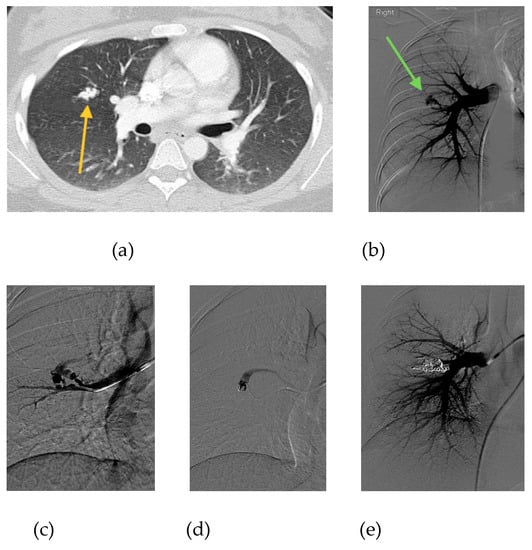

- Shimohira, M.; Kawai, T.; Hashizume, T.; Ohta, K.; Suzuki, K.; Shibamoto, Y. Pulmonary arteriovenous malformations: Current technique of transcatheter embolization and subsequent management. Interv. Radiol. 2017, 2, 116–121. [Google Scholar] [CrossRef][Green Version]

- Shimohira, M.; Kawai, T.; Hashizume, T.; Ohta, K.; Nakagawa, M.; Ozawa, Y.; Sakurai, K.; Shibamoto, Y. Reperfusion rates of pulmonary arteriovenous malformations after coil embolization: Evaluation with time-resolved MR angiography or pulmonary angiography. J. Vasc. Interv. Radiol. 2015, 26, 856–864. [Google Scholar] [CrossRef]

- Cusumano, L.R.; Duckwiler, G.R.; Roberts, D.G.; McWilliams, J.P. Treatment of recurrent pulmonary arteriovenous malformations: Comparison of proximal versus distal embolization technique. Cardiovasc. Interv. Radiol. 2020, 43, 29–36. [Google Scholar] [CrossRef]

- Hayashi, S.; Baba, Y.; Senokuchi, T.; Nakajo, M. Efficacy of venous sac embolization for pulmonary arteriovenous malformations: Comparison with feeding artery embolization. J. Vasc. Interv. Radiol. 2012, 23, 1566–1577. [Google Scholar] [CrossRef] [PubMed]

- Kajiwara, K.; Urashima, M.; Yamagami, T.; Kakizawa, H.; Matsuura, N.; Matsuura, A.; Ohnari, T.; Ishikawa, M.; Awai, K. Venous sac embolization of pulmonary arteriovenous malformation: Safety and effectiveness at mid-term follow-up. Acta Radiol. 2014, 55, 1093–1098. [Google Scholar] [CrossRef]

- Dinkel, H.P.; Triller, J. Pulmonary arteriovenous malformations: Embolotherapy with superselective coaxial catheter placement and filling of venous sac with Guglielmi detachable coils. Radiology 2002, 223, 709–714. [Google Scholar] [CrossRef] [PubMed]